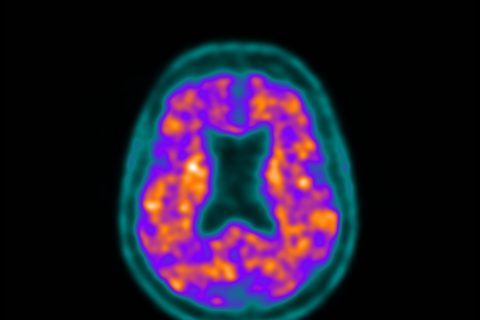

11C-Pittsburgh Compound B

Detecção de placas beta amiloides cerebrais que auxiliam na diferenciação de demências

11C-PK11195

Identificação de inflamação cerebral, ligadas a micróglia – células da linhagem dos monócitos.

Medicina Nuclear e Imagem Molecular em Neurologia e Psiquiatria

Desenvolvimento de radiofármacos e aplicação em modelos experimentais de quadros neurológicos com potencial aplicação translacional em:

- Estudos de processos neuroinflamatórios

- Envelhecimento normal

- Deficiência intelectual

- Doenças neurodegenerativas

Aplicações clínicas – MN, SPECT, PET/CT e PET/RM

Investigação de métodos de medicina nuclear e imagem molecular com finalidade diagnóstica, prognóstica ou acompanhamento terapêutico de doenças neurológicas e psiquiátricas:

- Esclerose múltipla

- Doenças degenerativas e envelhecimento

- Deficiência intelectual

- Transtornos do movimento

- Encefalopatia traumática crônica

- Zumbido